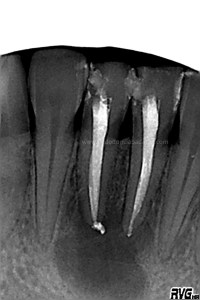

Debido al estudio anteriormente citado, se empezó a hacer el tratamiento de ortodoncia una vez que se comenzó a ver una evolución positiva, con signos claros de regeneración a los 6 meses .

(revisión a los 6 meses)